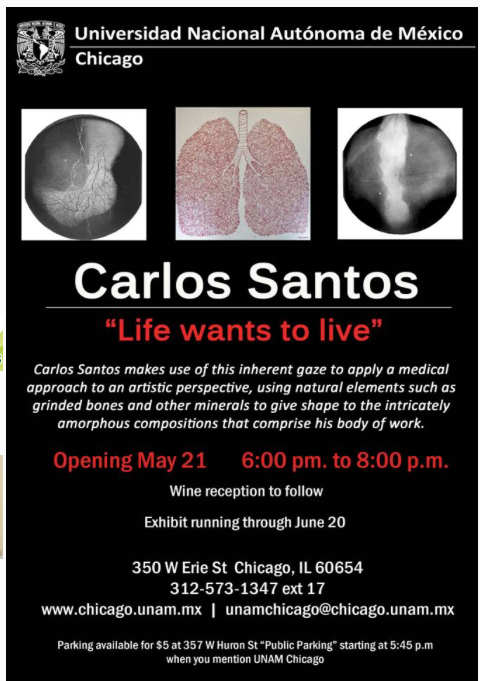

Life wants to Live

UNAM. Chicago Ilinois, USA.

2015

The temptation to appreciate the work of Carlos Santos is to be left admiring the expertise: embroidery, drawing, form, detail. A figure that at first glance looks human, transverse, X-rayed, contained bloody, is not “anatomy”: to say it is misleading. To say “rebuilt” is mono dimensional. “Altered” is descriptive. “Impossible,” preliminary.

Carlos’s work has red-arteria to be able to have a vein-blue, it takes root to have branches, it imitates human to grow as a vegetable. It goes beyond the body but inward, to feel that the epidermis is not even the first limit.